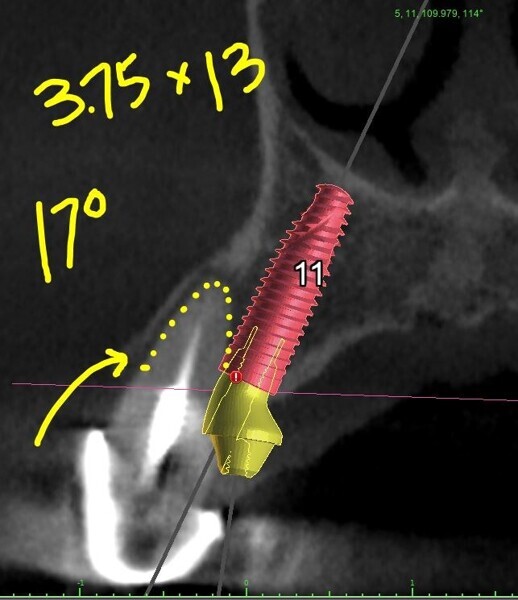

Each potential implant receptor site was designated by tooth number for the maxillary and mandibular arches. Manufacturer-specific simulated implants were then refined within the cross-sectional images, recording diameters and lengths in screenshots for the maxilla (Fig. 4) and the mandible (Fig. 5) utilised during the surgery as colour printouts.

Figs. 5a–e: Implant planning for the mandibular arch with straight and angled multi-unit abutments.